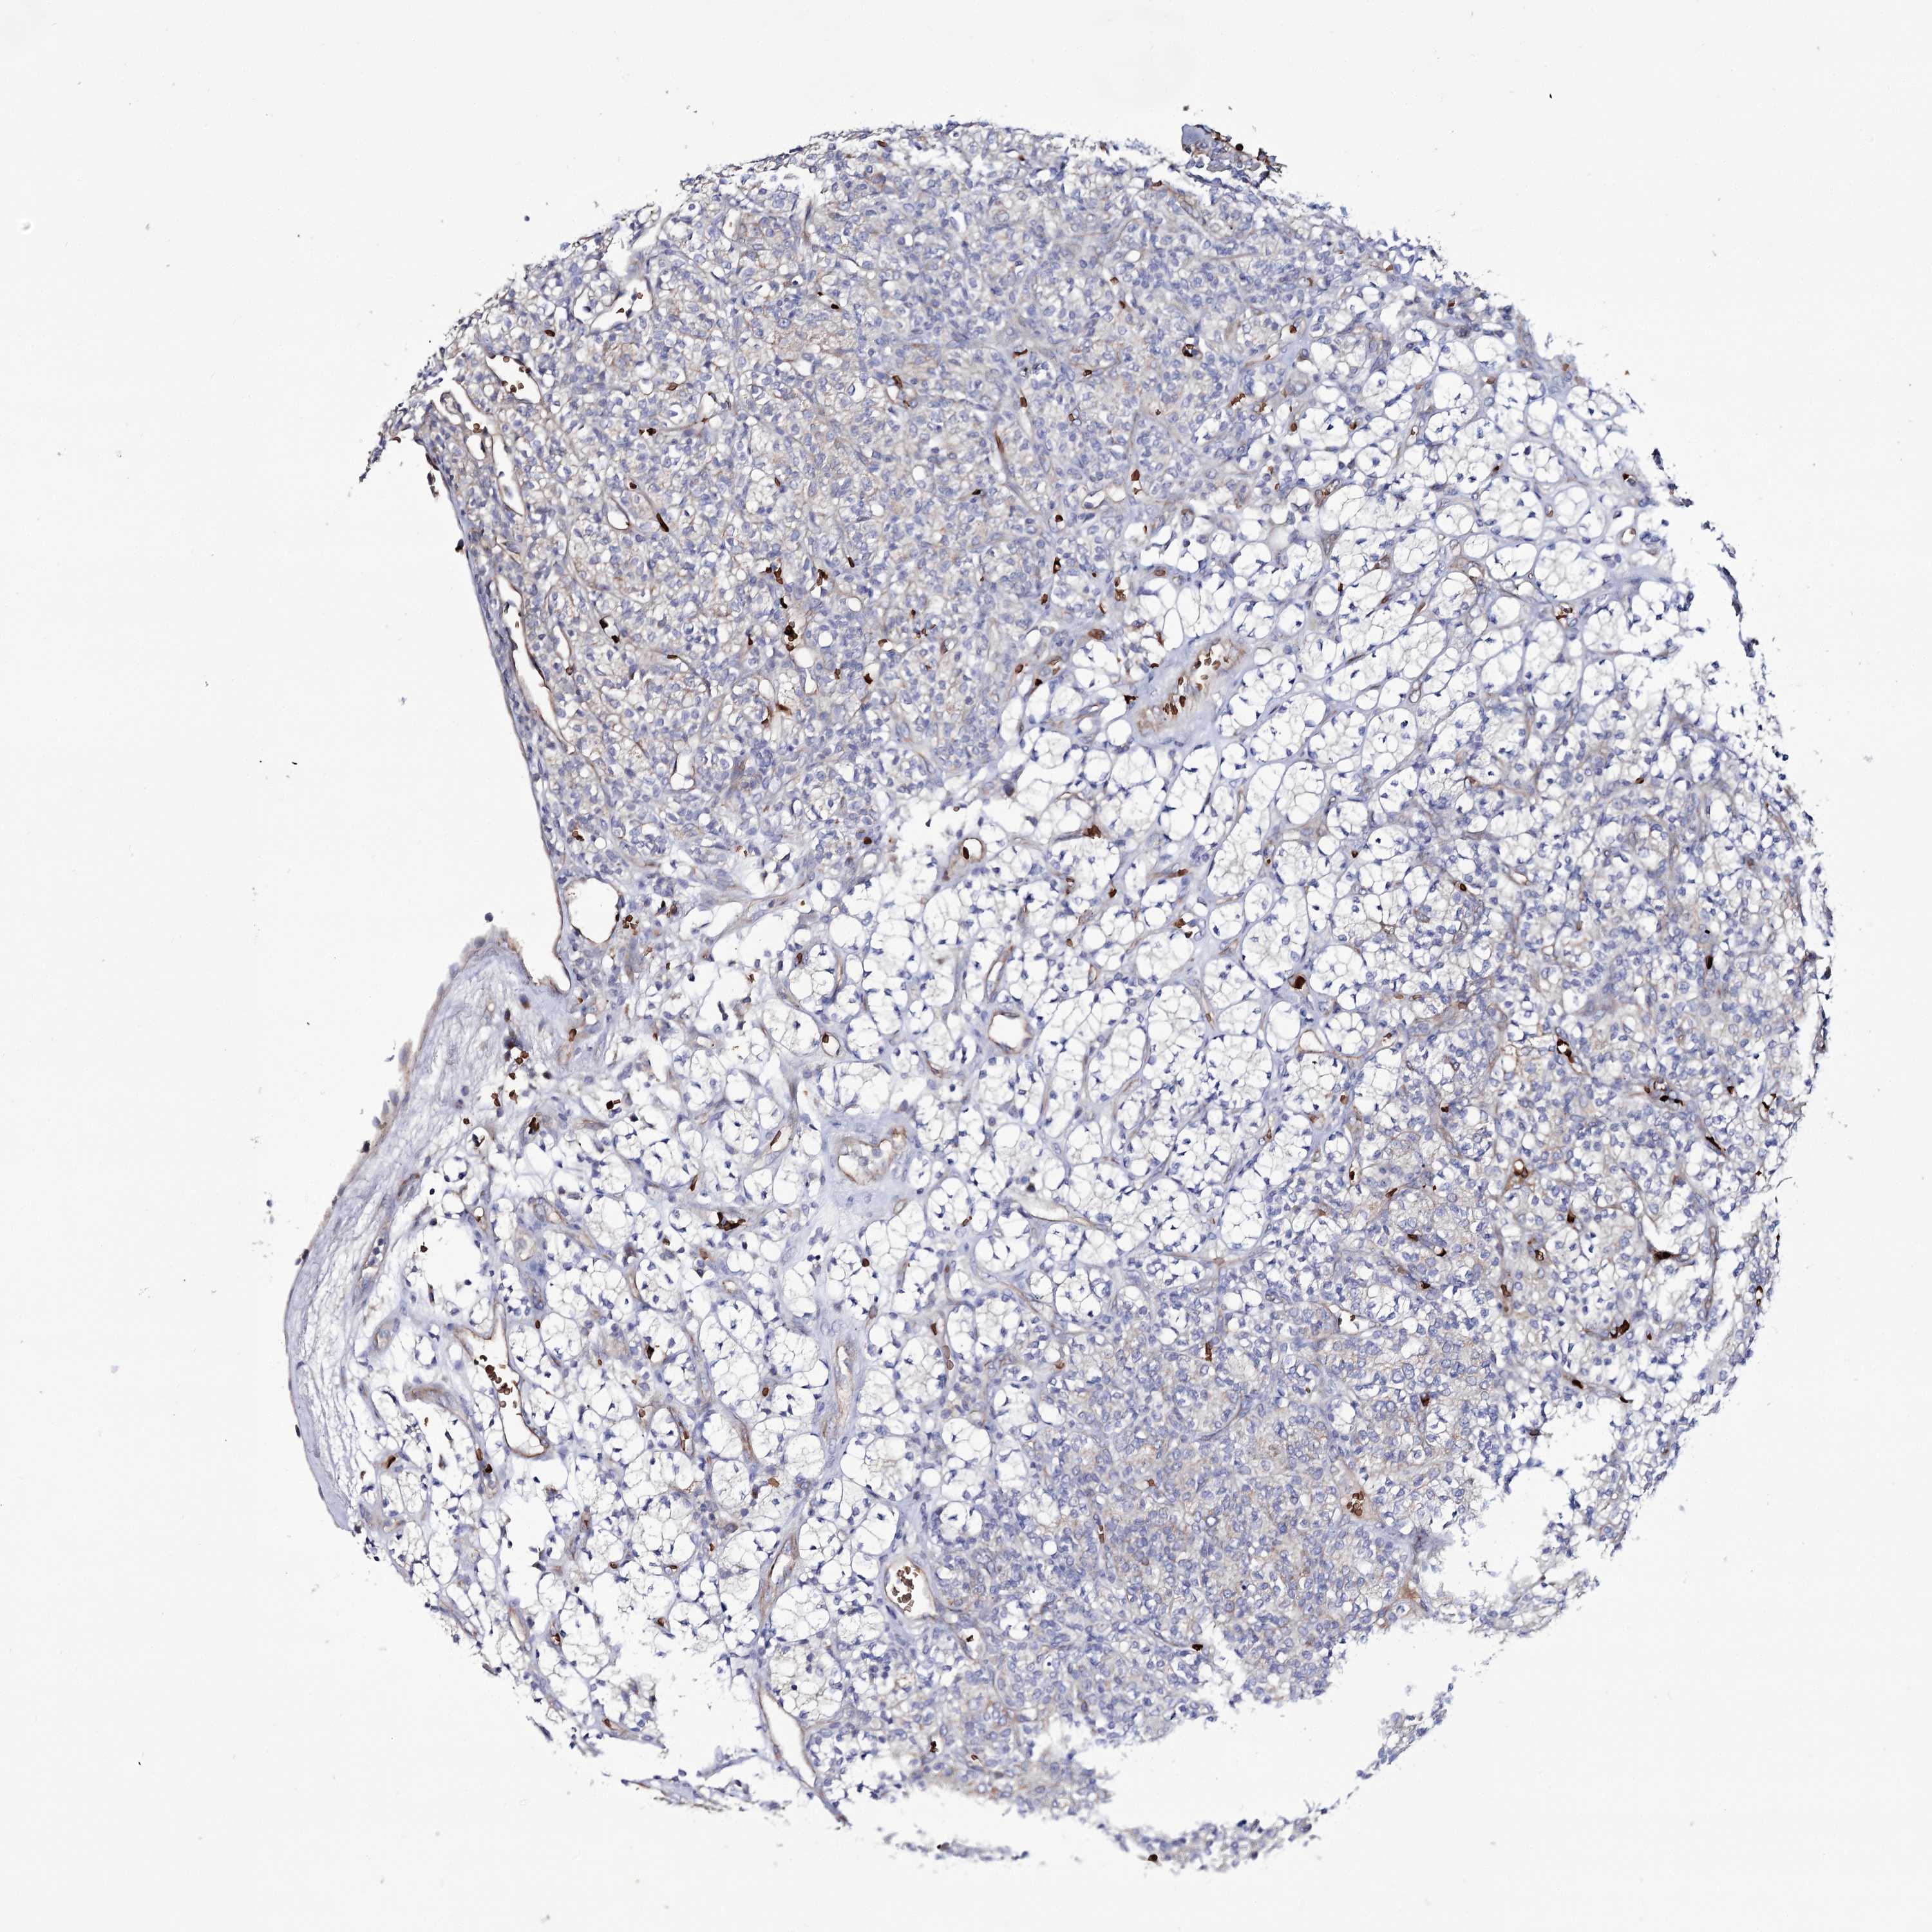

KIDNEY RENAL CLEAR CELL CARCINOMA (VALIDATION) - Interactive survival scatter ploti

The Survival Scatter plot shows the clinical status (i.e. dead or alive) for all individuals in the patient cohort, based on the same data that underlies the corresponding Kaplan-Meier plots. Patients that are alive at last time for follow-up are shown in blue and patients who have died during the study are shown in red.

The x-axis shows the expression levels (FPKM) of the investigated gene in the tumor tissue at the time of diagnosis. The y-axis shows the follow-up time after diagnosis (years). Both axes are complimented with kernel density curves demonstrating the data density over the axes. The top density plot shows the expression levels (FPKM) distribution among dead (red) and alive patients (blue). The right density plot shows the data density of the survived years of dead patients with high and low expression levels respectively, stratified using the cutoff indicated by the vertical dashed line through the Survival Scatter plot. This cutoff is automatically defined based on the FPKM cutoff that minimizes the p-score. The cutoff can be changed by dragging the vertical line or by entering a cutoff value in the square labeled "Current cut-off".

Under the Survival Scatter plot the p-score landscape (black curve; left axis) is shown together with dead median separation (red curve; right axis). Dead median separation is the difference in median mRNA expression between patients who have died with high and low expression, respectively. It is calculated as follows: median FPKM expression of dead patients with high expression - median FPKM expression of dead patients with low expression. This is intended to aid the user in visually exploring custom cutoffs and the associated p-scores and dead median separation.

Individual patient data is displayed and can be filtered by clicking on one or more of the category buttons on the top of the page. Categories describing expression level and patient information include: high, low, alive, dead, female, male and tumor stages. The scale of the x-axis can be toggled between linear and log-scale by clicking on the "x log" button. Mouse-over function shows TCGA ID, patient information and mRNA expression (FPKM) for each patient.

& Survival analysisi

Kaplan-Meier plots summarize results from analysis of correlation between mRNA expression level and patient survival. Patients were divided based on level of expression into one of the two groups "low" (under cut off) or "high" (over cut off). X-axis shows time for survival (years) and y-axis shows the probability of survival, where 1.0 corresponds to 100 percent.

GBF1 is not prognostic in Kidney Renal Clear Cell Carcinoma (validation)

Best expression cut offi

Based on the FPKM value of each gene, patients were classified into two groups and association between prognosis (survival) and gene expression (FPKM) was examined. The best expression cut-off refers the FPKM value that yields maximal difference with regard to survival between the two groups at the lowest log-rank P-value. Best expression cut-off was selected based on survival analysis .

When clicking on this number, the vertical dashed line indicating cut-off, the interactive survival plot, and the Kaplan-Meier curve will be adjusted to show results based on the best expression cut-off.

: 25.29

TCGA RNA samplesi

RNA-seq data is reported as average FPKM (number Fragments Per Kilobase of exon per Million reads), generated by the The Cancer Genome Atlas (TCGA) .

Normal distribution across the dataset is visualized with box plots, shown as median and 25th and 75th percentiles. Points are displayed as outliers if they are above or below 1.5 times the interquartile range. FPKM values of the individual samples are presented next to the box plot.

Average pTPM 20.6

Number of samples 100